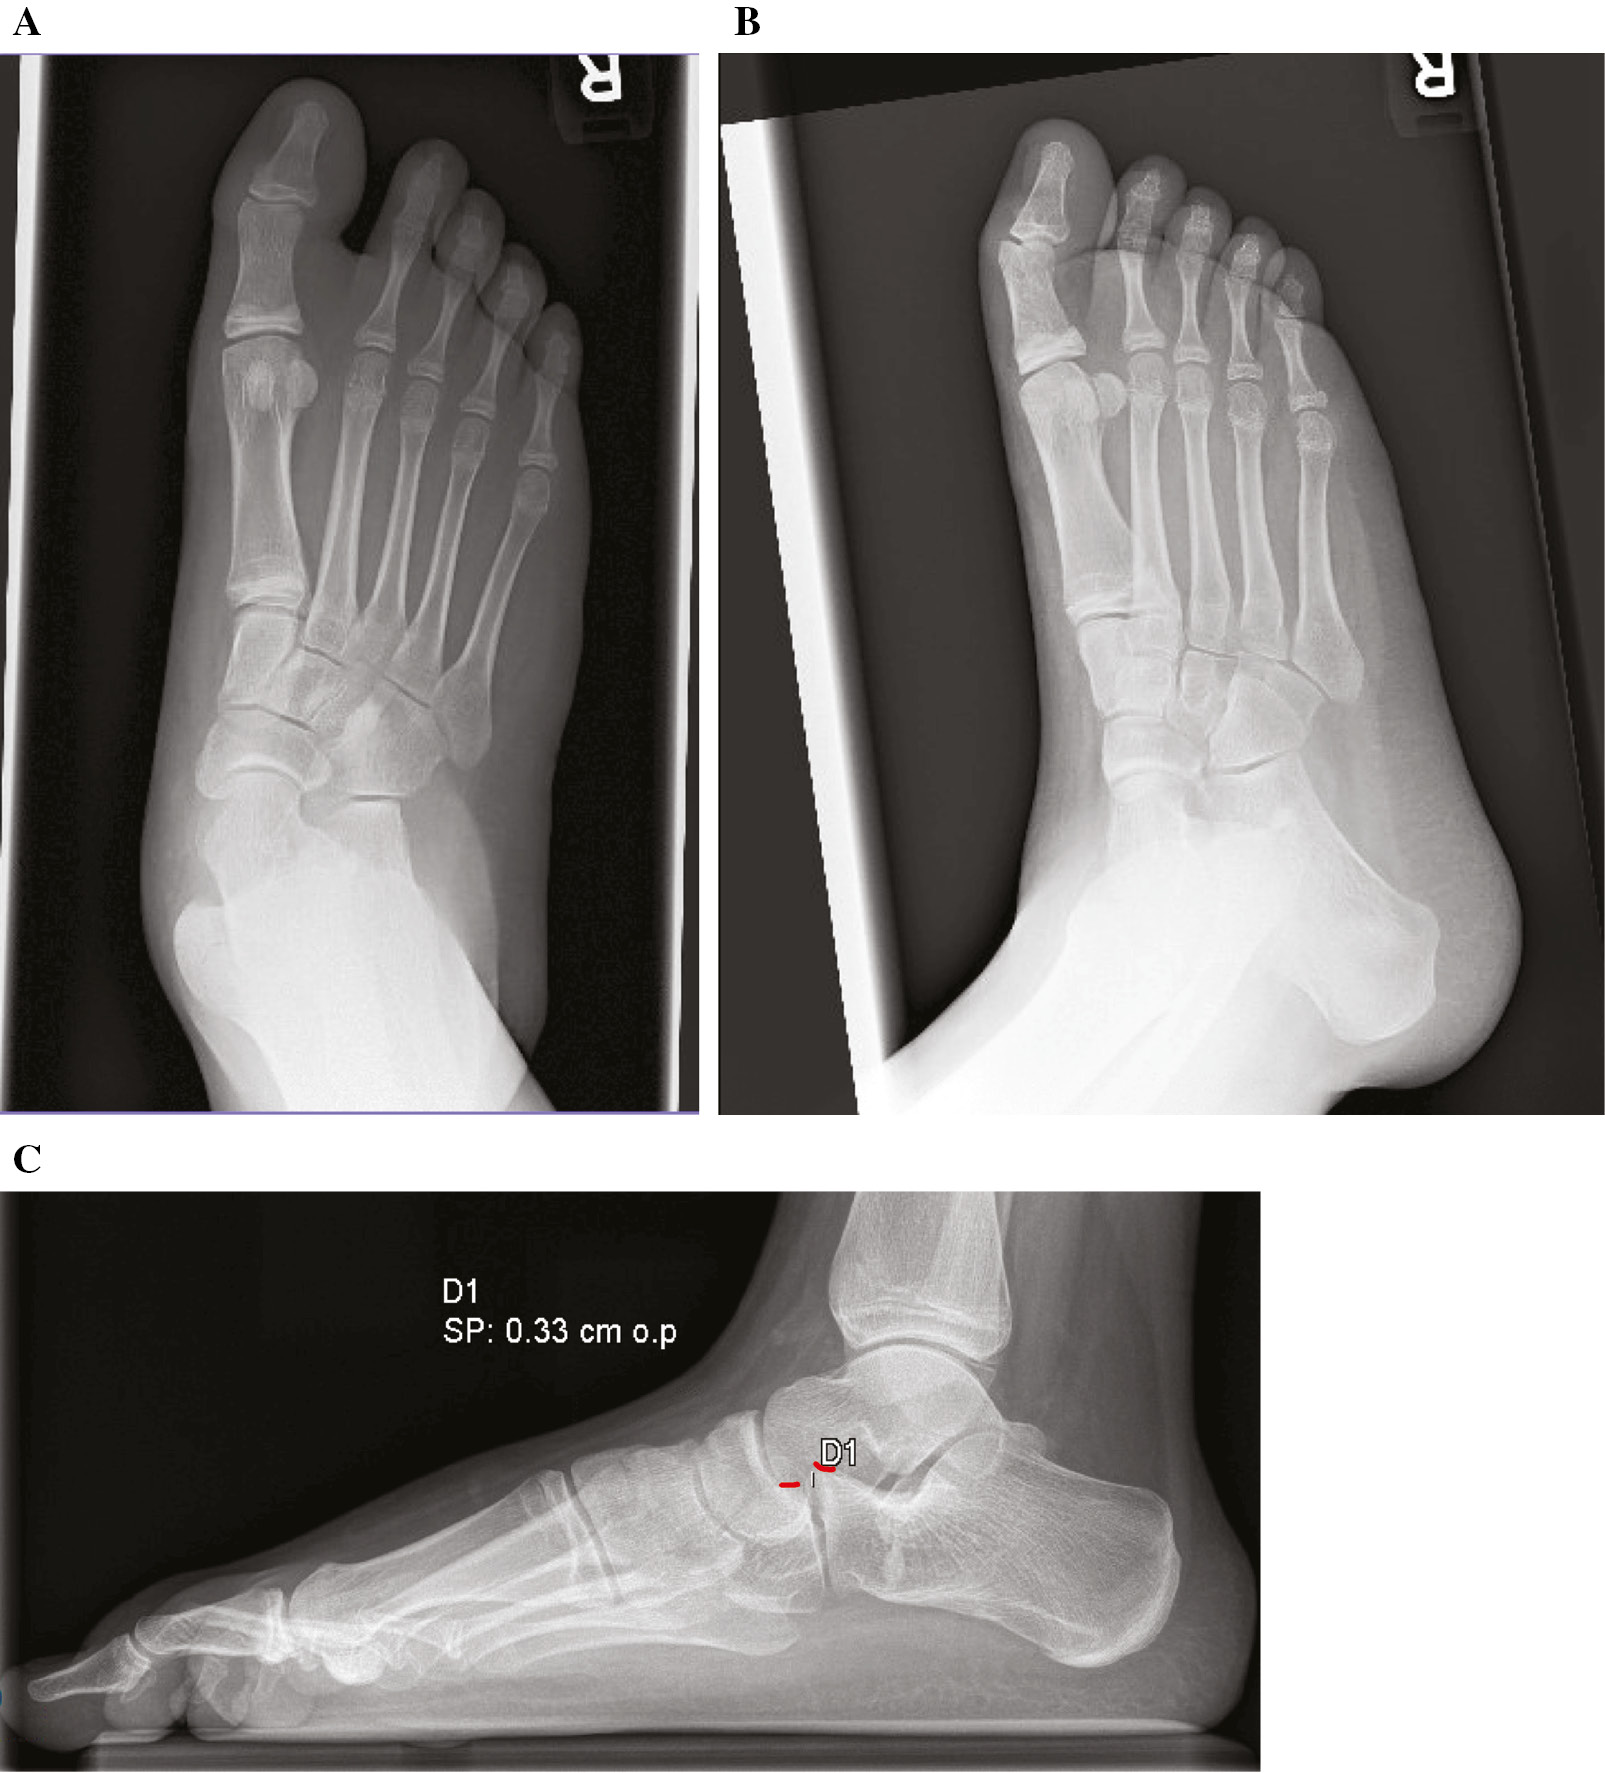

The patient underwent a right lateral column lengthening, peroneus brevis lengthening, posterior tibial tendon and medial talonavicular capsular reefing, and percutaneous Hoke Achilles tendon lengthening. The forefoot was mildly plantarflexed and inverted to facilitate pinning of the CC joint (Figure 2). Notably, the lateral radiograph shows a difference in the CC relationship compared to the preoperative standing radiograph with the cuboid displaced plantar to the distal calcaneus. Postoperatively, he was treated with a short-leg cast and remained non-weight bearing until his 6-week postoperative follow-up at which time the pin was removed and he was transitioned to a controlled ankle motion (CAM) boot and instructed to weight bear as tolerated. Radiographs at that visit still show persistent CC subluxation (Figure 3). At the 12-week postoperative follow-up, the patient is without symptoms referable to the CC joint, but radiographs show persistent subluxation (Figure 4).

Figure 2. Lateral radiograph after pinning of CC joint and before calcaneal osteotomy. Red lines represent dorsum of calcaneus and cuboid.

Figure 3. (A) AP and (B) lateral 6-week postoperative radiographs demonstrating persistent CC joint subluxation.

jposna2022567_fig3.jpg

Figure 4. (A) AP and (B) lateral 12-week postoperative radiographs demonstrating persistent CC joint subluxation following pin removal.

jposna2022567_fig4.jpg